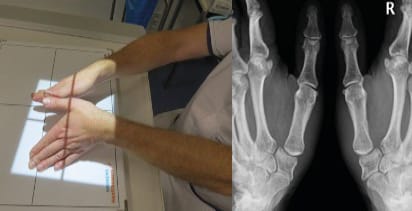

Eaton’s views are the same as Kapandji’s frontal view, except that in the Eaton series the images are comparative (Figure 4), which means that a stress view (Figure 5) is taken so that the joint space can be assessed for any collapse when put under stress.

It is important to reiterate that radiology of the thumb base is not capable of reflecting patient pain (Figure 11). A patient showing Dell stage 1 (or Eaton stage 1 or a TMA1, TMI 0 and STT 0) may be in very significant pain, which may make them a candidate for joint replacement surgery (Figure 10).